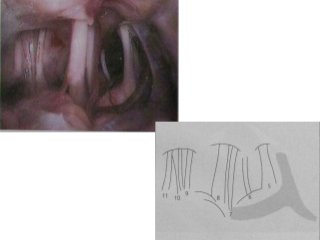

Fig. 74a, b The reference level is the acousticofacial nerve

bundle. The anterior inferior cerebellar artery, lying between

the auditory and facial nerves, is found in 38% of cases.

7up- 7th is above

Coca cola – cochlear n. is cola[=lower]